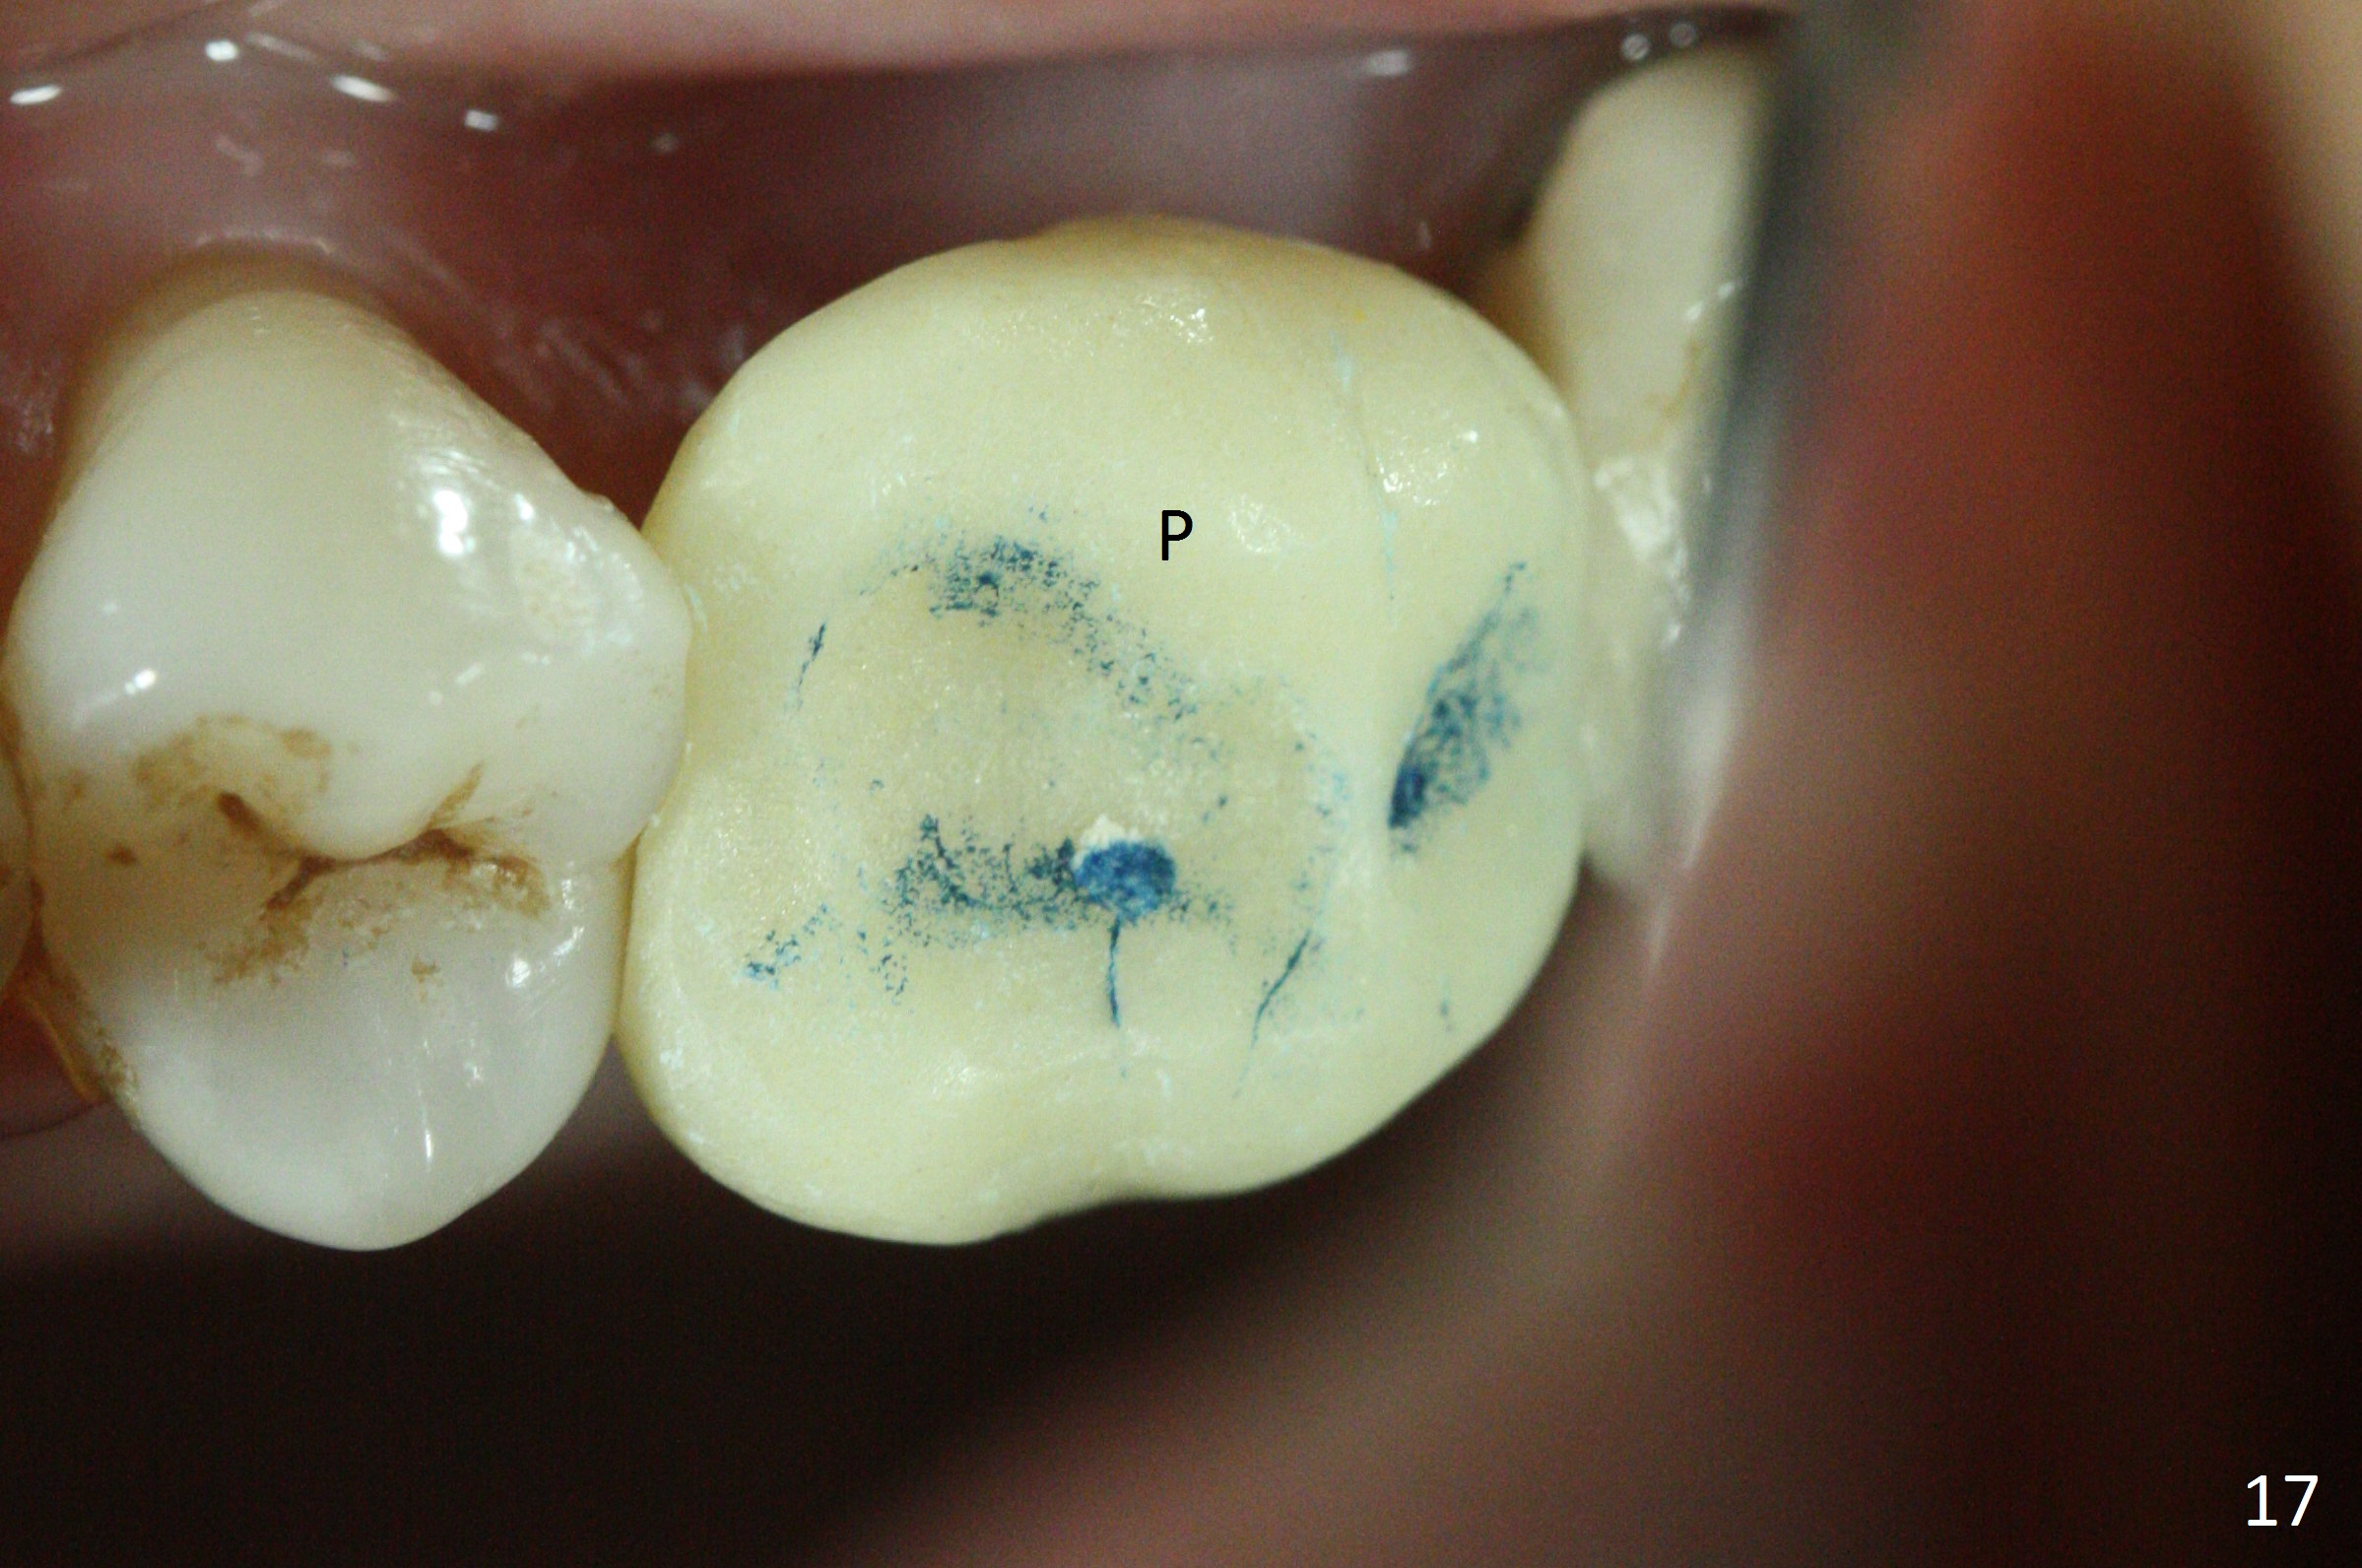

The implant is stable 8 months postop (Fig.15). When a 6x4(3) mm abutment is placed 8.5 months postop, it is distal (Fig.16). The mesiodistal width is 1-2 mm shorter than that at #3, which suggests the mesial shift of the tooth #15. A provisional is fabricated at #14 (Fig.17 P) with supra-occlusion so that there is clearance between the tooth #15 and the opposing one (Fig.18 *). With a separator placed between #14 and 15 (Fig.19), the latter is free to be distalized. Bone volume and density seem to increase 4.5 and 10.5 months post cementation (Fig.20,21, as compared to Fig.15), although the buccal plate remains as concave as shown in Fig.18. One year 5 months post cementation, the patient complains of bad smell from the implant when water pik is being used. It appears that the 1st 2-3 threads are exposed (Fig.22), although the surrounding gingiva remains uninfected. Bone graft is recommended. The site heals without bad smell 7 months post bone graft (2 years 4 months post cementation, Fig.23). The 1st implant thread is found exposed buccal on uncover (regraft?). A small healing abutment is placed because the implant is placed distal (Fig.24). An angled abutment should be tried and #15 crown will be redone. Impression will be taken when the gingiva heals around the provisional crowns.